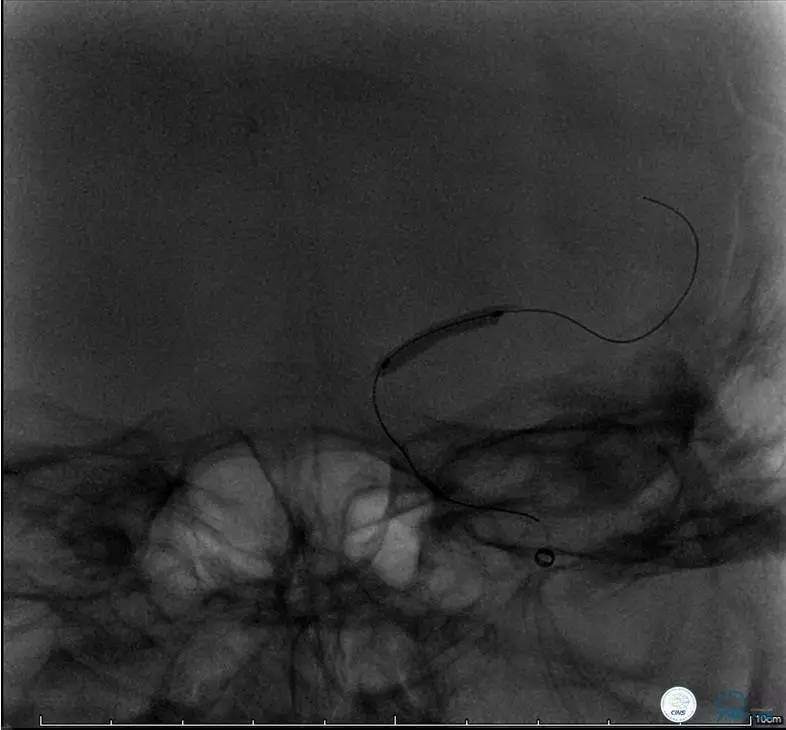

造影评价血管、判断闭塞段,微导丝谨慎穿过闭塞段,微导管造影,交换技术,球囊扩张,Enterprise支架。在后扩张时导丝刺破M3段血管,蛛网膜下腔出血(SAH)。

微导管进入破裂血管,栓塞弹簧圈1枚,出血停止,结束手术。继续双抗,术后2天肌力2级,神经功能恢复明显加快。

术后即刻和6天后CT,患者无明显临床症状。

半年后复查造影,无支架内再狭窄,可见弹簧圈,患者恢复至自己柱杖行走。